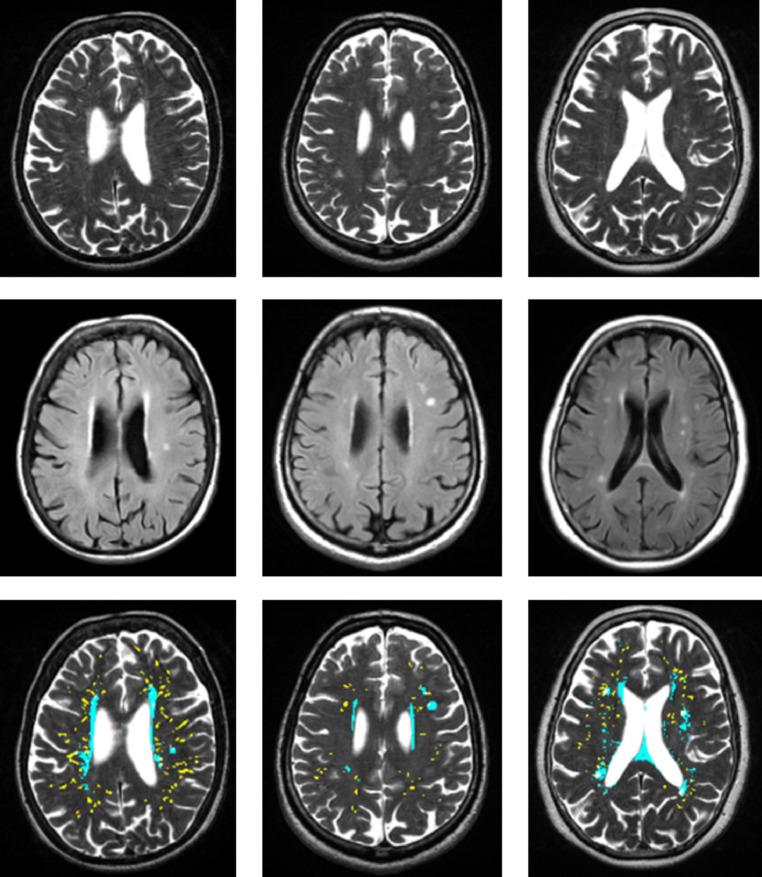

Computational quantification of brain perivascular space morphologies: Associations with vascular risk factors and white matter hyperintensities. A study in the Lothian Birth Cohort 1936.

Perivascular Spaces (PVS), also known as Virchow-Robin spaces, seen on structural brain MRI, are important fluid drainage conduits and are associated with small vessel disease (SVD). Computational quantification of visible PVS may enable efficient analyses in large datasets and increase sensitivity to detect associations with brain disorders. We assessed the associations of computationally-derived PVS parameters with vascular factors and white matter hyperintensities (WMH), a marker of SVD.

We assessed PVS computationally in the centrum semiovale and deep corona radiata on T2-weighted images. The computationally calculated measures were the total PVS volume and count per subject, and the mean individual PVS length, width and size, per subject. We assessed WMH by volume and visual Fazekas scores. We compared PVS visual rating to PVS computational metrics, and tested associations between each PVS measure and vascular risk factors (hypertension, diabetes, cholesterol), vascular history (cardiovascular disease and stroke), and WMH burden, using generalized linear models, which we compared using coefficients, confidence intervals and model fit.